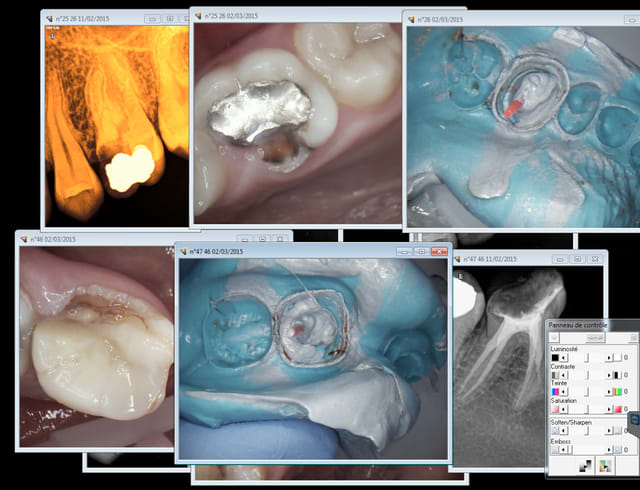

Tu t'occupes de santé publique, hein ? Alors je vais t'expliquer comment ca se passe à long terme sur le terrain grace à la merveilleuse nomenclature de ce système collectiviste de merde :

Endo pourries à un tarif de merde- coiffes...... extractions........ bridge ......... extractions- complet immédiat.

Tu es sur que tu sers à quelque chose ? quelle réussite ! -))))

Big up pour la CCAM ultra moderne ( bridges) qui va dans le bon sens !

Ca fait toujours son effet un complet immédiat, un plaisir à gérer pour le praticien et le patient !

Capture d e cran 2015 03 02 21.50 - Eugenol

Capture d e cran 2015 03 02 21.52 - Eugenol

Apparement ,nos tetes pensantes ont décidés qu'il était plus simple

de leur donner le DROIT d'avoir du 4 à 4 céramisés (payés 8000 euros pour les 2 arcades) plutot que le DEVOIR d'utiliser une brosse à dent souples à 4 euros .